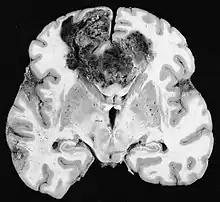

Glioblastoma

Os tumores de células gliais mais comuns e malignos são os glioblastomas. Consistem em uma massa heterogênea de células de astrocitoma pouco diferenciadas principalmente em adultos. Geralmente ocorrem nos hemisférios cerebrais, mais raramente no tronco cerebral ou na medula espinhal. Exceto em casos muito raros, como todos os tumores cerebrais, eles não se estendem além das estruturas do sistema nervoso central.

O glioblastoma pode surgir de uma forma difusa (II. grau) ou um astrocitoma anaplásico (III. grau) se desenvolvem. Neste último caso, é chamado de secundário. No entanto, quando ocorre sem antecedentes ou evidência de malignidade prévia, é referido como primário. Os glioblastomas são tratados com cirurgia, radioterapia e quimioterapia. Eles são difíceis de curar e há poucos casos que sobrevivem além de três anos.

No tecido tumoral, em geral, a maior proporção de realce pelo contraste se deve à barreira hemato-tumor particular que permite a passagem de iodo (TC) e gadolínio (RM) para o espaço intersticial extravascular intratumoral. Isso aumenta o sinal (densidade ou intensidade) do tumor. No entanto, deve-se ter cuidado para garantir que o realce do contraste não diferencie definitivamente a neoplasia do edema periferida. De fato, o achado anátomo-patológico no tecido tumoral de glioma infiltrante maligno, como no glioblastoma e no astrocitoma anaplásico, também mostra além do edema vasogênico causado pela destruição da barreira hematoencefálica pelo tumor. Esta última condição clínica é pouco detectável pelo diagnóstico por imagem.

Na ressonância magnética, um tumor intracraniano aparece como uma lesão maciça que pode se tornar mais luminescente após o uso do agente de contraste. No entanto, há sempre uma anomalia de sinal na ressonância magnética, que indica a presença de neoplasia ou edema vasogênico. Normalmente, o aumento da luminescência (realce pelo contraste) é indicativo de um tumor de grau mais alto de malignidade. Um anel contrastante é característico do glioblastoma, com a porção luminescente correspondendo à parte vital do tumor maligno e a área mais escura-hipointense à necrose tecidual.